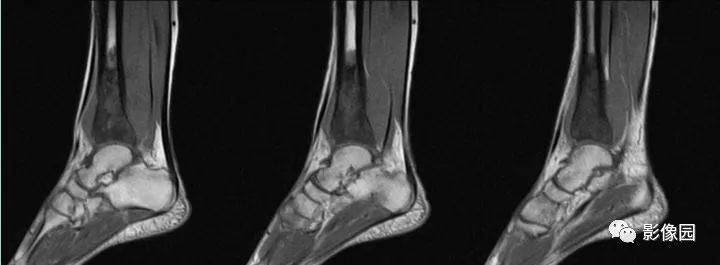

2016-05-11复查

评论:前片X线示左胫骨下段及干骺端病变,髓腔内密度不均匀增高,内侧骨皮质可见骨质破坏,可见骨膜反应。CT示病灶内见多发斑片状肿瘤骨(黄色箭头),周围可见针状骨膜反应(红色箭头)。周围软组织肿胀。MRI示胫骨下段以长T1、长2信号为主的混杂信号影,未跨越胫距关节面,周围未见明显软组织肿块。周围软组织广泛片状长T1长T2信号影。复查X线示病变较前片明显进展,左侧胫骨远段及干骺端骨质破坏,周围可见针状骨膜反应及Codman三角(蓝色箭头)形成。相邻左侧腓骨下端、距骨滑车受累。